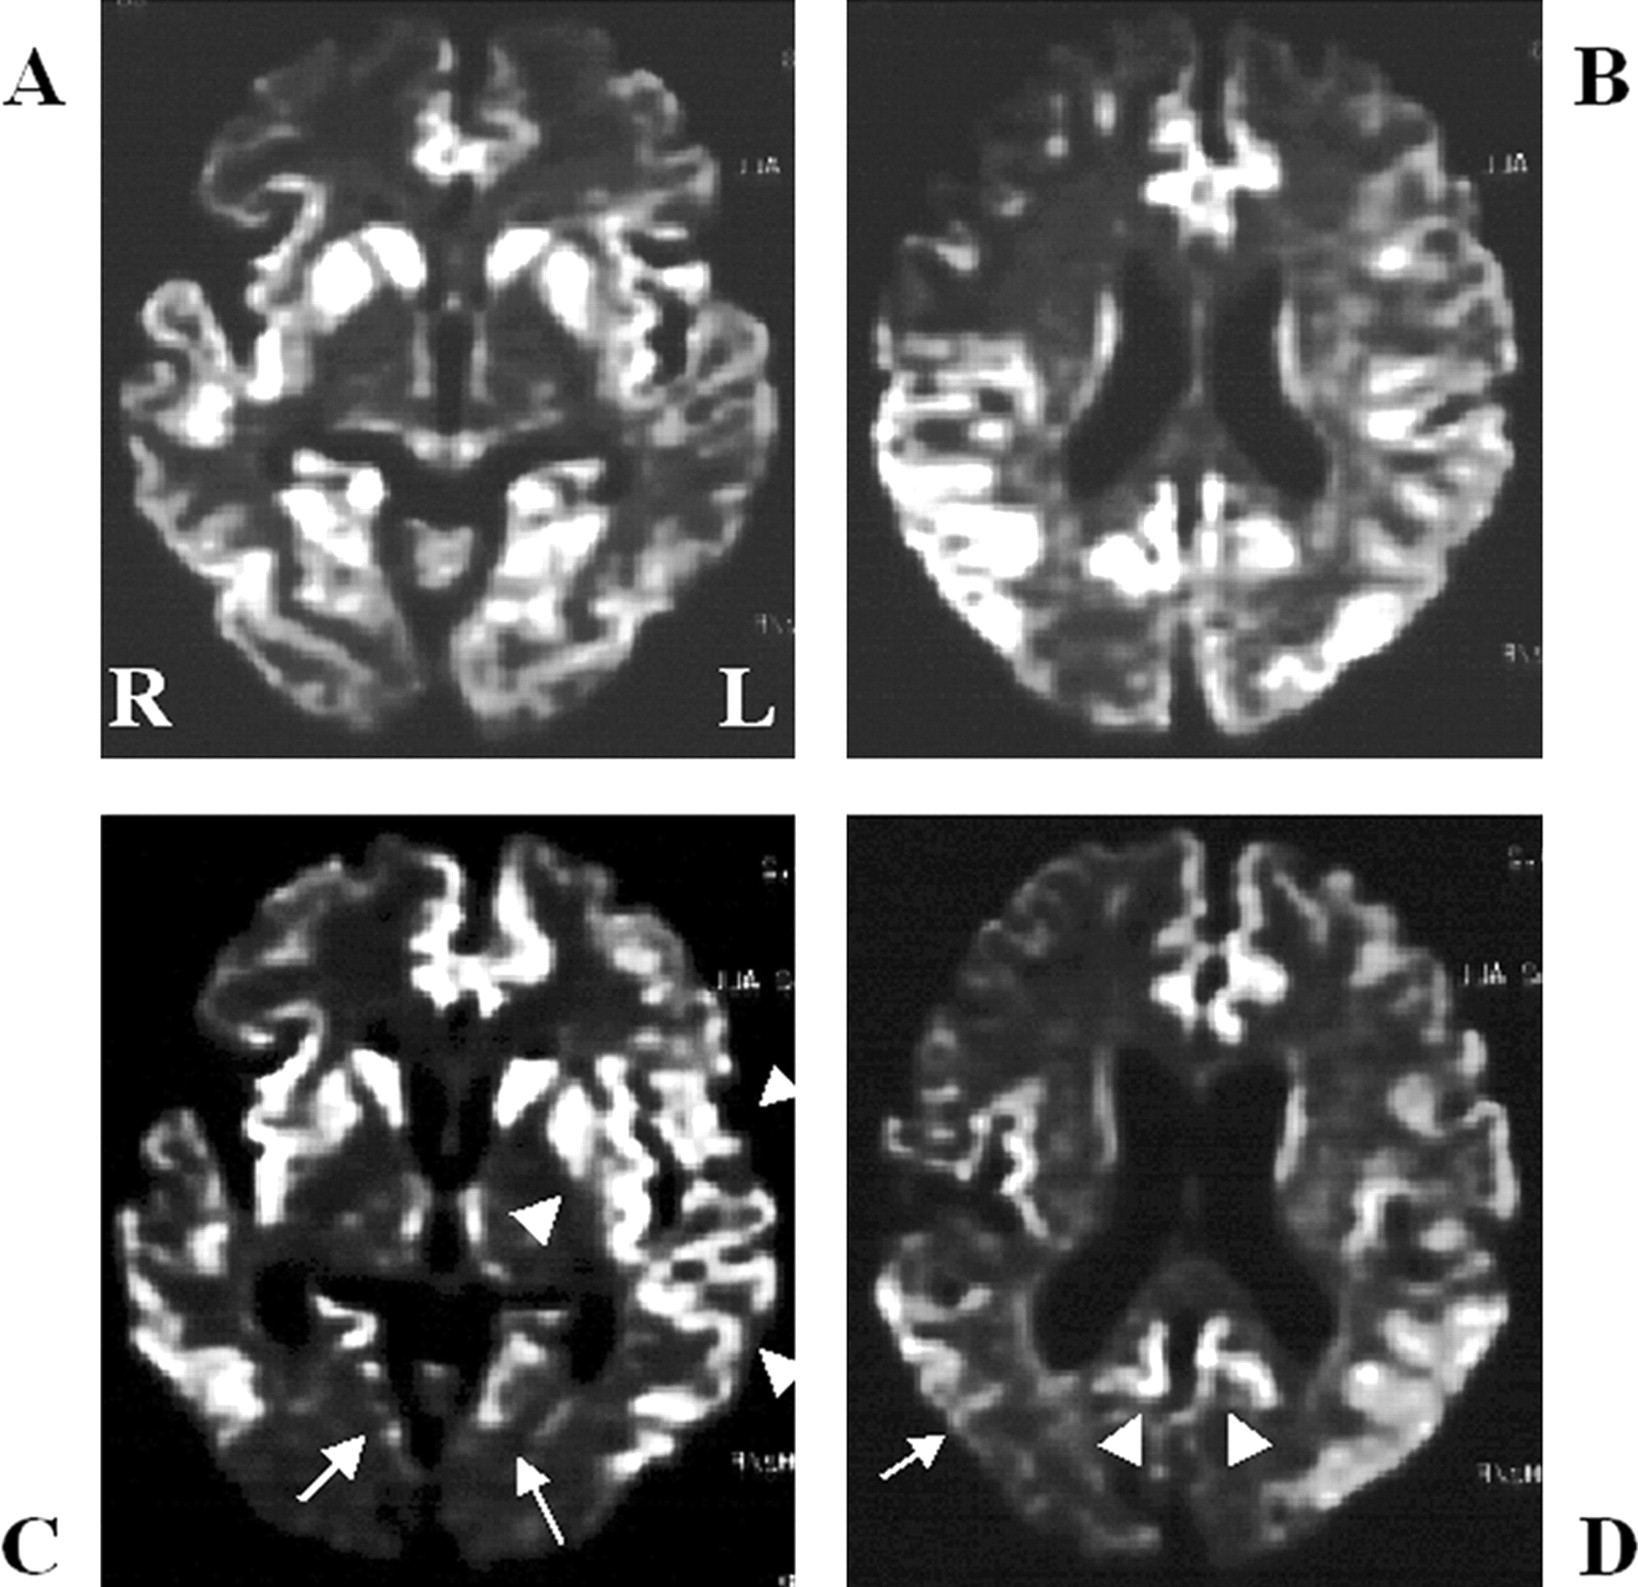

酒后驾驶是在26日检查库贾氏症患者发病后3到25周平均持续时间为10.7周。24库贾氏症患者表现出高强度脑损伤的驾车考试。两个观察者,醉酒驾车的库贾氏症诊断的敏感性为92.3%。interobserver协议率为100%。3例(12.5%)显示只在尾状头和硬膜损伤,10例(41.7%)患者显示线性损伤只有在大脑皮层,和11例(45.8%)患者显示病变基底神经节和大脑皮层(图1)。其中,只有三个病人(12.5%)显示,丘脑病变。没有病人显示高强度在小脑病变。高强度损伤在驾车之前出现脑萎缩。病变包括纹状体初并不总是对称的但是后来对称(图2),尽管对称的纹状体病变是众所周知的在库贾氏症。11在某些情况下,高强度损伤与连续驾车并不总是进展的疾病,而有时信号强度降低了疾病进展的一些病变。在某些情况下,皮质高信号强度不同,解剖分布(图3)。在终端阶段与深刻的脑萎缩,高强度损伤变得不清楚。T2I DWI-examined 26日在23日检查病人,但T2I扫描被排除在外,因为低质量由于运动构件。一位观察家认为11 22患者阳性(50.0%),而另一个观察者认为8阳性(36.4%)。interobserver协议率为68.2%,低于酒后驾车(p< 0.005)。在这两个观察者,醉酒驾车是比T2I更敏感(p一个观察者,< 0.005p另一个观察者p < 0.0005)。天赋是17 26患者的检查。一位观察家认为10 17例阳性(58.8%),和另一个观察者认为7是积极的(41.2%)。interobserver协议率为82.4%,也低于酒后驾车(p< 0.05)。醉酒驾车是比天赋更敏感(p一个观察者,< 0.01p另一个观察者p < 0.0005)。我们在图4一个例子中,只有醉酒驾车可以检测高强度异常病变。

图2。按时间顺序的改变的纹状体和皮质病变。零星的克雅氏病(CJD)显示基底神经节的进展信号变化不对称对称(B) (A)。(A)和(B)之间的间隔是2个月。的家族与V180I突变库贾氏症显示大脑皮层的进展和尾状核头信号变化不对称(C)对称(D)。(C)和(D)之间的间隔是4个月。

图3。按时间顺序的改变皮质病变的零星克雅二氏症(sCJD)。皮质高强度在sCJD随着时间的推移而改变的情况下,增加和减少信号强度在不同的地区。高强度的双边枕叶皮层(A)减少(C,箭头),而信号强度在左岛和颞皮层(A)明显增加(C,箭头)。(一)和(C)之间的间隔是1个月。右颞叶皮层的高强度和双边枕叶皮层(B)减少(D,箭头为左颞叶皮层和箭头双边内侧枕叶皮层)。(B)和(D)之间的间隔是1个月。注意,高强度损伤中描述diffusion-weighted成像并不是简单地扩大疾病的进展。